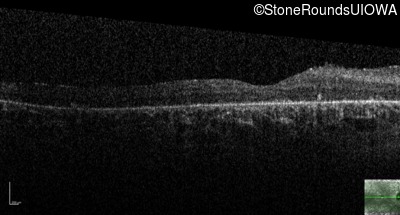

Visit at age: 28 years

Optical Coherence Tomography - Right - Hand Motion

Exemplar / OCT Stack

OCT Stack